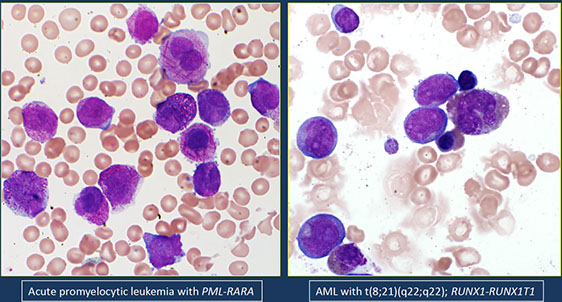

- Acute promyelocytic leukemia (APML) with PML-RARA

- Acute myeloid leukemia with t(8;21)(q22;q22.1); RUNX1-RUNX1T1

- Acute myeloid leukemia with inv(16)(p13.1q22) or t(16;16)(p13.1;q22); CBFB-MYH11